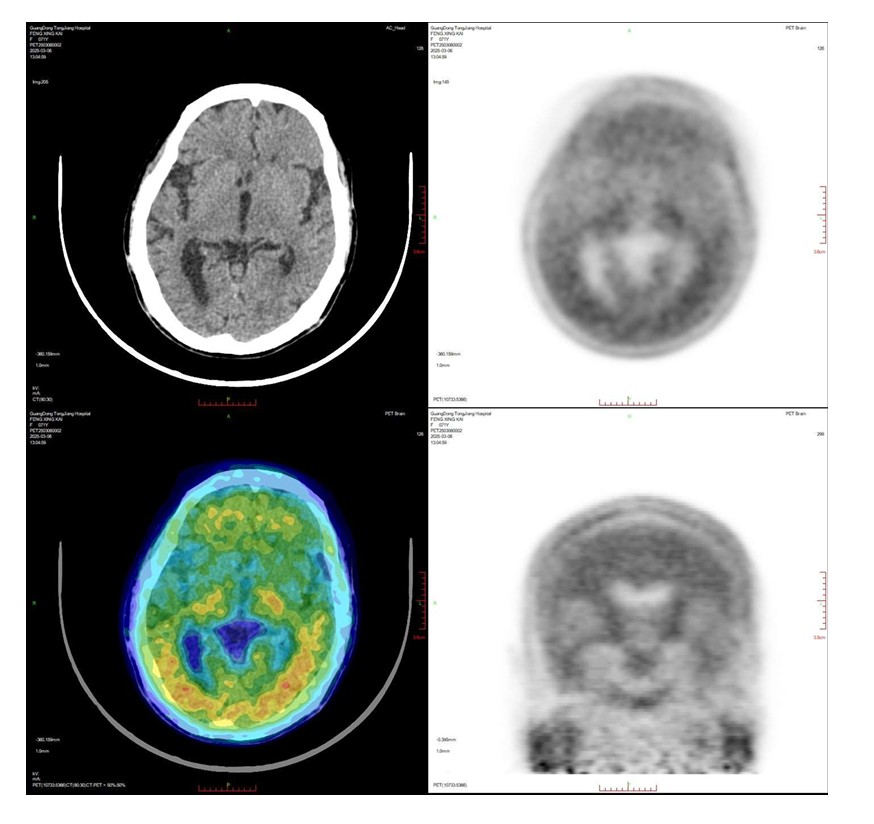

2025年3月4日,国内首款Aβ-PET显像剂获得批文,使得β-淀粉样蛋白正电子发射断层扫描技术早期诊断AD成为现实。该技术可以“锁定”患者脑内的致病蛋白沉积,可以在症状出现前10-15年前精准诊断AD,还可用于靶向治疗的疗效监测,解决了早发现早治疗AD的关键性难题。

2025年3月4日,ky获批β-淀粉样蛋白正电子发射断层扫描技术。3月6日早上,临床诊断为阿尔茨海默病的冯阿姨,成为佛山首批接受该项检查的患者。周思朗副院长、核医学科周世辉主任、神经内科董晓莉主任、老年科丘伟贤主任和设备技术专家一起,顺利完成了β-淀粉样蛋白正电子发射断层扫描。ky还安排了高质量的远程会诊,让首批病例的报告质量达到了行业的高水平。

Aβ-PET检查,患者仅需静脉注射微量放射性显像剂,等待90分钟后,20分钟可完成全身扫描。该技术高效无创,通过图像量化脑内淀粉样斑块的分布与浓度,进行精准诊断和病情评估。